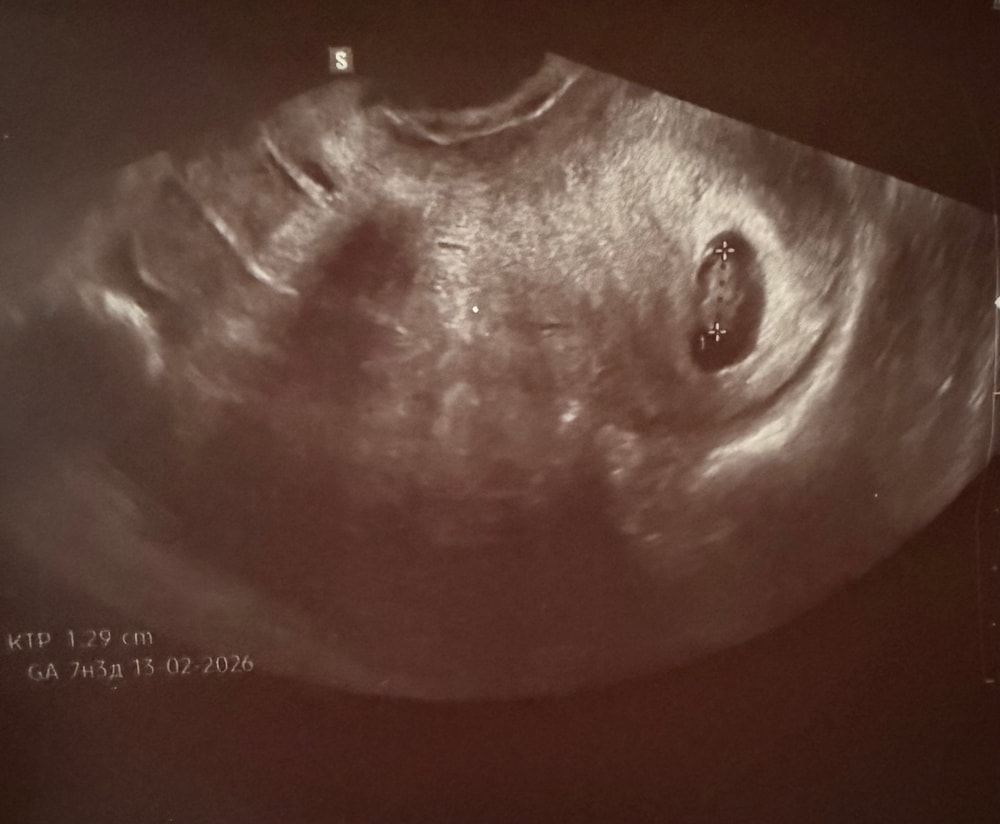

Узи, 7 недель 4 дня

Беременность- 1 триместр ( только до 10 недель)Сходила на узи послушать сб, посмотреть на фасолинку ☺️

Все хорошо 🙏🏼 тьфу-тьфу!